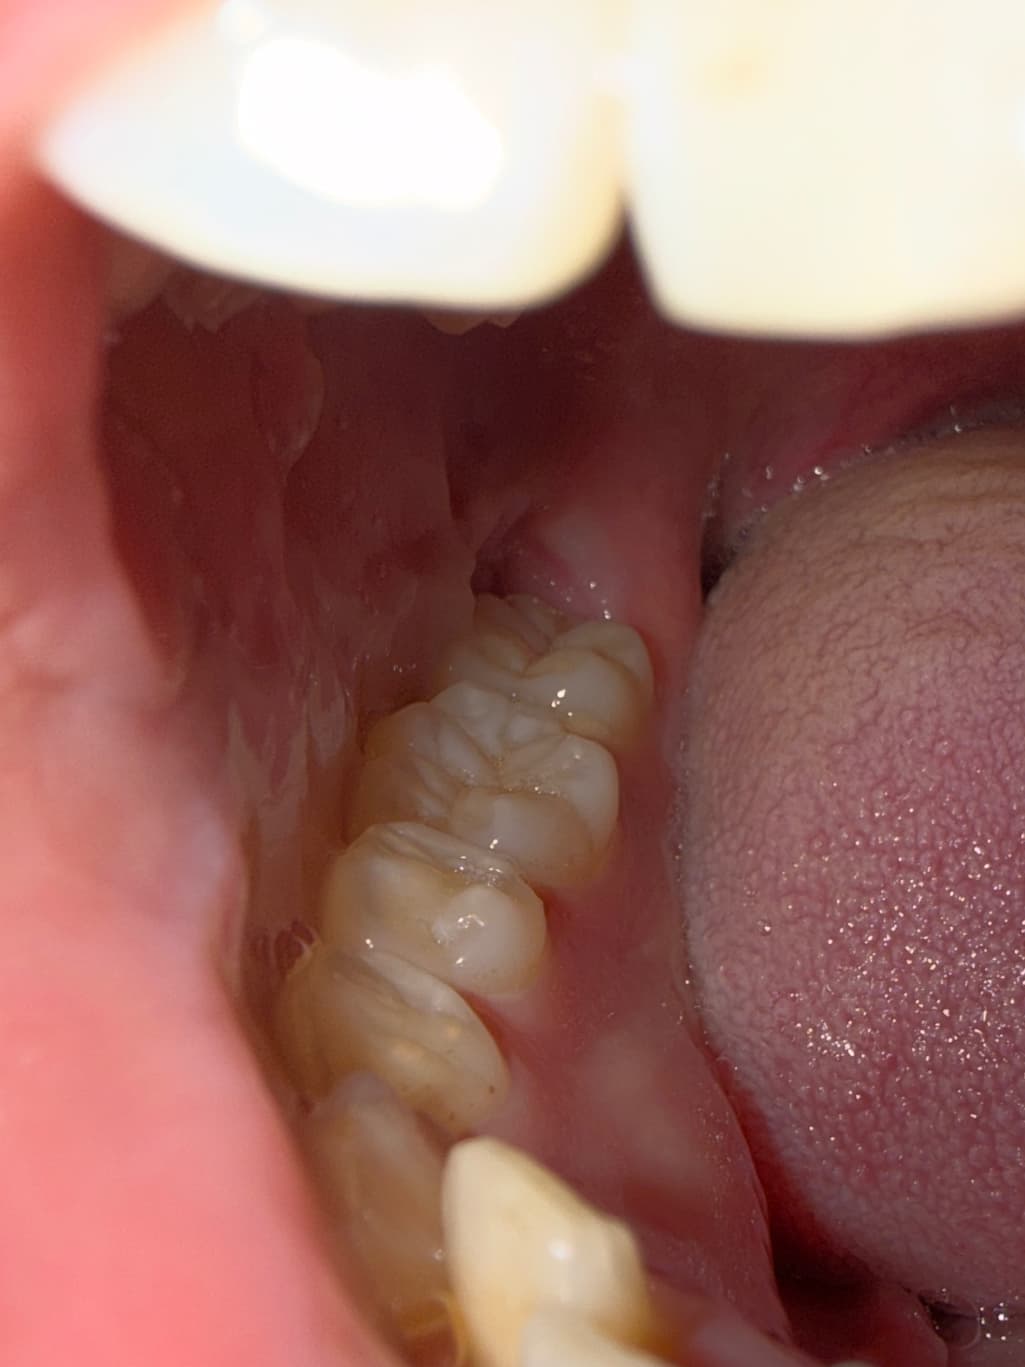

사랑니 발치 5일차 인데 아직 통증이 있는데 괜찮은건가요 ? -> 통증과 별개로 사진상 잇몸 치유는 잘되고 있는 것 같습니다.드라이소켓이 발생하면 통증은 어느정도고 악취는 어느정도 인가요..? -> 아주 심합니다